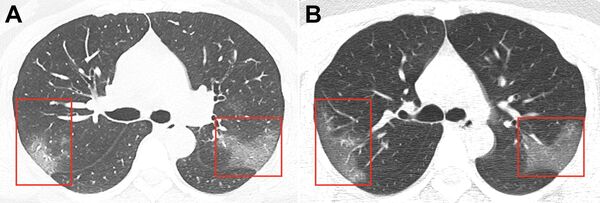

Ảnh chụp lá phổi bị ảnh hưởng bởi coronavirus